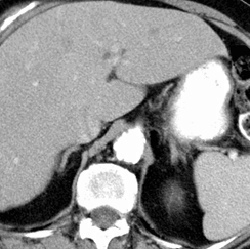

RADIOLOGY: ABDOMEN: Case# 32908: MULTIFOCAL EXTRA-ADRENAL MYELOLIPOMA. This is a 73 year old female with a history of abnormal pap smear. She had prior history of hysterectomy and bilateral salpingo-oophorectomy as well as mastectomy for breast cancer. A large ill-defined soft tissue mass measuring approximately 4.5x5.8cm (image 41) is seen in the pre-sacral region. This mass has both soft tissue as well as fat density in it. The liver is enlarged at 19cm without any focal lesions evident in it. The spleen is normal in size and configuration without any focal lesions evident. Two large simple renal cysts are noted involving the left upper pole and mid region. The larger cyst in the mid region measures 4x4cm in its anterior posterior and transverse dimension. There is minimal dilatation of the common duct at approximately 11mm which is slightly above the limits for post-cholecystectomy patient. The uterus is absent surgically. No adnexal masses are identified in the pelvis. No intra-abdominal or pelvic lymph nodes are identified. Multiple posterior mediastinal paraspinal nodular masses are seen, the largest node measuring 1.5x2.0cm in its transverse and anterior posterior dimension. A rare nonfunctional tumor consisting of bone marrow and fatty tissue, extra-adrenal myelolipoma is usually unilateral and asymptomatic. The incidence on autopsy is 0.2% to 0.4%. On CT, this tumor appears as a well-defined mass of up to 30 cm in diameter with inhomogeneous central fat density. The fat content within any given tumor is variable such that a lesion may appear as a predominantly fatty mass with a surrounding thin rim of soft tissue to a lesion of predominantly soft tissue density with small regions of fat. These tumors are avascular and do not demonstrate contrast enhancement. High density areas may be present secondary to prior hemorrhage. Calcifications may be present, and the tumor may appear to extend into the perinephric tissue. CT is usually diagnostic, but biopsy or percutaneous needle aspiration may be necessary.